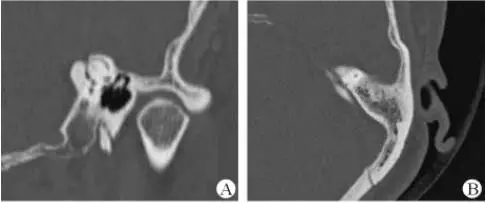

1、上半規管裂綜合征

內耳結構非常微妙。即使是內耳中大頭針樣的孔洞也能造成平衡失調。患者常常不敢進行如走路或轉頭的日常活動。此罕見疾病,醫學專家預估至少影響著人口的1%。可造成惡心,眩暈以及對噪聲極高的敏感性。病人還常常抱怨他們能聽到血管跳動的聲音。其中一位患者曾告訴耳科專家,他都能聽到自己轉動眼睛的聲音。

診斷及治療

醫生若懷疑此病將會安排內耳CT掃描。在大多數案例中,一旦此病被耳鼻喉科醫生或其它聽力健康專家確診,則可實行手術治療。外科手術風險包含聽力損失以及神經損傷;重建及復原需內耳的治療以及大腦的重塑。